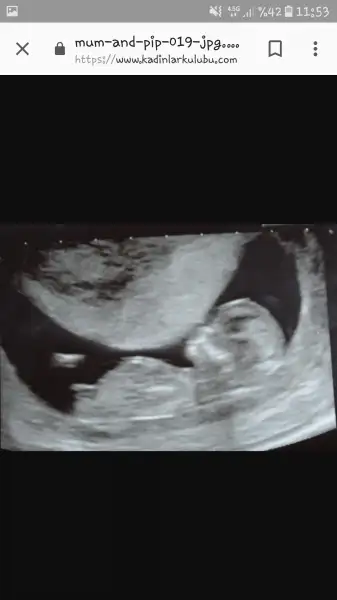

Arkadaşlar diyince ben de az önce buldum o konuyu. :)))) Emin oldum gibi ben demorceket ayrıca genital nub cıkıntısana gore de paralel gözüküyor Kız gibi sağlıklı bi evladın olur inşallah :)

evet evet bazısınkinde cok net gözüküyor o cıkıntıArkadaşlar diyince ben de az önce buldum o konuyu. :)))) Emin oldum gibi ben deGerçekten çok barizmiş. Apaçık ortada. Allah o teoriyi bulandan razı olsun. Doktorum da sağ olsun gerçekten çok net yakalamış. :)